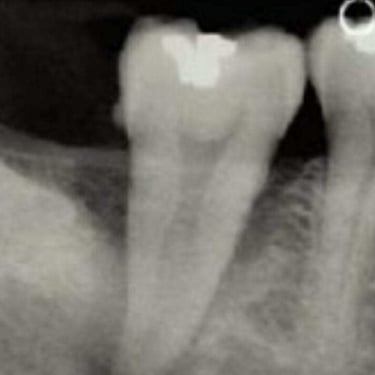

Calcificación Pulpar

La calcificación pulpar es la formación de depósitos de calcio dentro de la pulpa dental, que puede dificultar el tratamiento de conducto.

Los pacientes generalmente no tienen síntomas, pero pueden experimentar sensibilidad.

El tratamiento incluye la eliminación de los depósitos durante el tratamiento de conducto. Es importante tratarlo para evitar complicaciones durante el procedimiento.